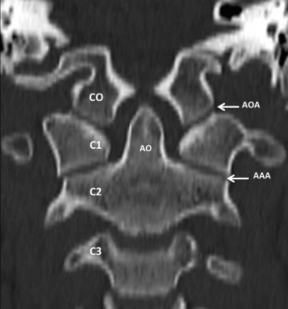

Luego encontramos a C1 formada por un arco anterior y otro posterior con sus masas laterales donde se ubican las superficies articulares que articulan con los CO y con C2 (►Fig. 2). Por último se suma C2 que contribuye con superficies articulares ubicadas en la cara superior de sus sectores laterales y en la apófisis odontoidea (AO) (►Fig. 3).

TCMD, VR, vista oblicua superior de C2. Se muestra la 2ª vértebra cervical o axis en una vista desde arriba que muestran sus diferentes sectores de relación con C1. Abreviaciones: AO, apófisis odontoidea de C2.

Está formada por ambas AOA de disposición lateral, y sus medios de unión. Vincula la base del cráneo con el raquis cervical y está formada por articulaciones de tipo condíleo que se disponen a ambos lados de la línea media de forma simétrica (►Fig. 4). Por su geometría permite movimientos en los 3 planos del espacio aunque los más amplios son los de flexo-extensión.

TCMD, reconstrucción coronal, ventana ósea. Se muestra una vista anterior del raquis sub-occipital y las articulaciones que forman parte de la UCC. Abreviaciones: AAA, articulación atloido-axoidea; AOA, articulación occipito-atolidea; CO, cóndilo occipital; C1, 1ª vértebra cervical; C2, 2ª vértebra cervical; C3, 3ª vértebra cervical.